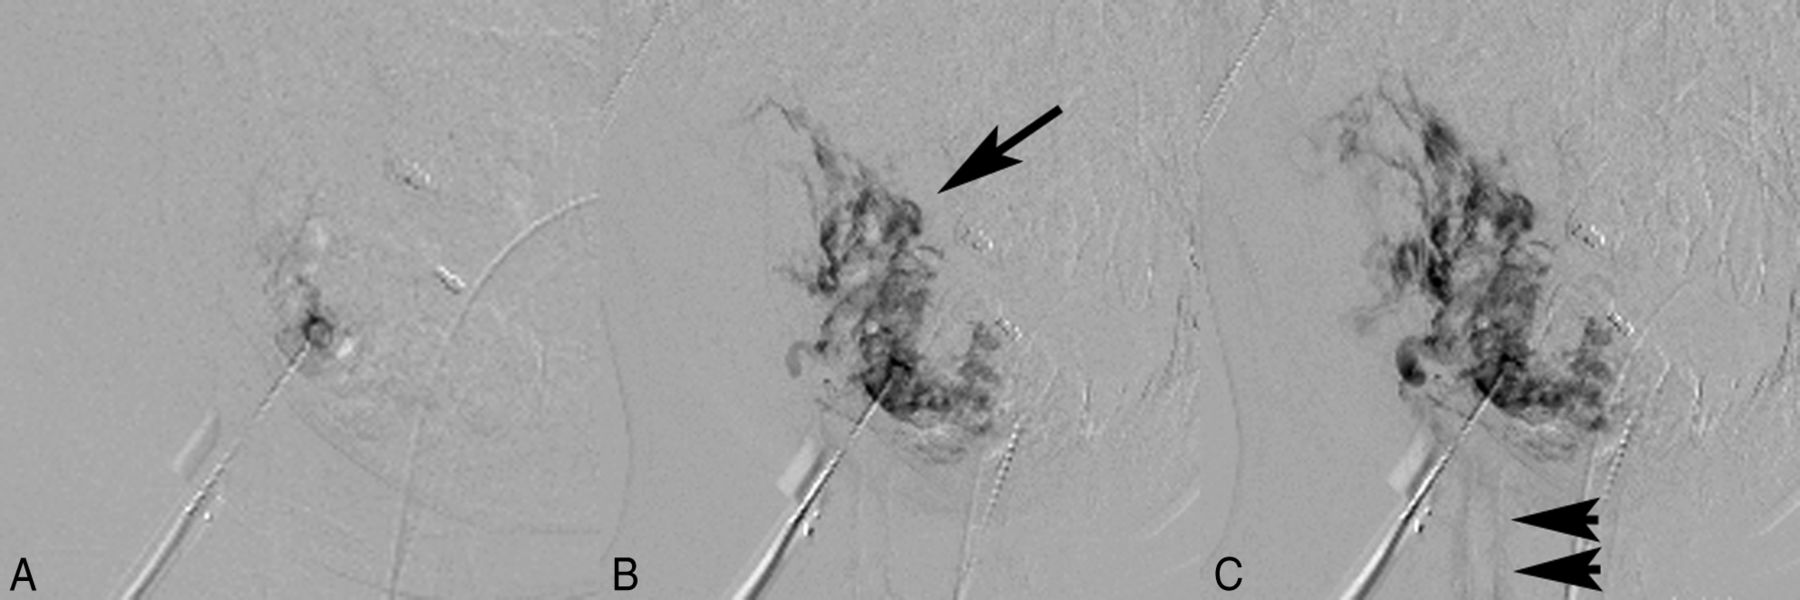

A 10-year-old girl with a very large venous malformation of the right face, who has had >20 previous treatment episodes with traditional digital subtraction angiography guidance, now being treated with MR imaging guidance. These images demonstrate the necessity of angiography to assure proper needle positioning. Coronal (A) and axial (B) T2-weighted fat-saturated MR images show the very large venous vascular malformation extending essentially throughout all superficial and deep spaces of the right face, producing significant local mass effect. C, Pretreatment MR angiogram, initial needle placement, demonstrates opacification of the venous malformation but also a focus of stagnation of contrast material that remained on the late-phase images, indicating extravasation (arrow). Thus, this is not a safe location to treat, and sclerotherapy was not performed. Note that normal venous backflow from the needle hub was initially detected, but adequate needle placement can only be assured following angiography. Early (D) and late (E) phase pretreatment MR angiograms, second needle placement, again demonstrate opacification of the venous malformation but now also show runoff of the contrast material on the late-phase image, indicating safe needle placement for embolization (arrowheads). Note the continued presence of the previously extravasated contrast material from the first injection on this nonmask subtracted image (arrows). F, Early-phase pretreatment MR angiogram, third needle placement, depicts needle localization within the venous malformation; however, there is very rapid filling of an enlarged draining vein (arrow). Thus, this is not a safe location to treat, and sclerotherapy was not performed. Again, adequate needle placement can only be assured following angiographic visualization of the lesion. Patient photographs before (G) and following (H) MR sclerotherapy show significant improvement in right facial swelling; however, a persistent right facial venous malformation is still present, requiring additional multiple future treatment sessions.